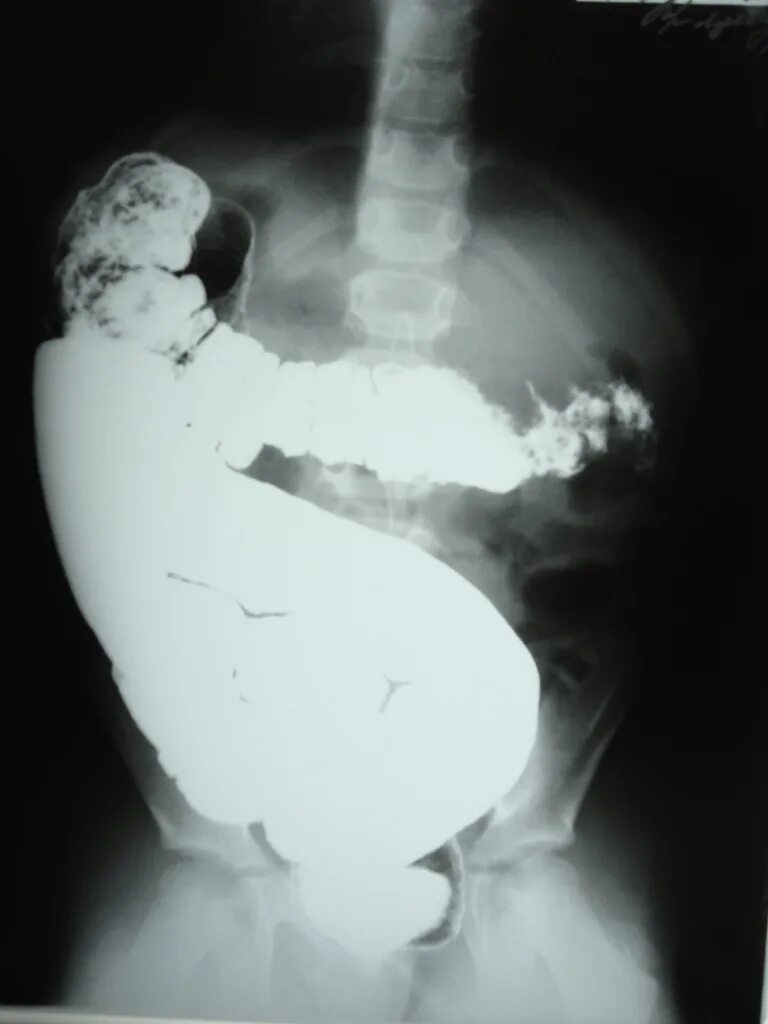

Долихоколон симптомы у взрослых